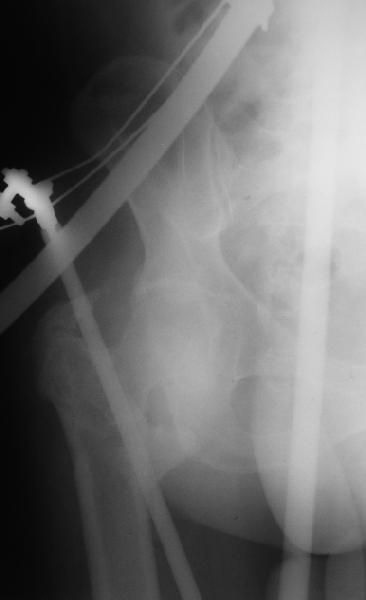

На прошлой неделе оперировали похожего пациента. 2 года после неудачного остеосинтеза PFN в другом регионе. После удаления остатков железа выявилось несращение вертельной области.

Поскольку в нашем случае выявилась подвижность, мы наложили дистрактор таз-бедро на 3 дня, и сделали остеосинтез гаммой без остеотомии. То, что произошла "корригирующая остеоклазия" в подвертельной области, выявили после введения гвоздя. Пациент уже уехал домой, будем наблюдать.